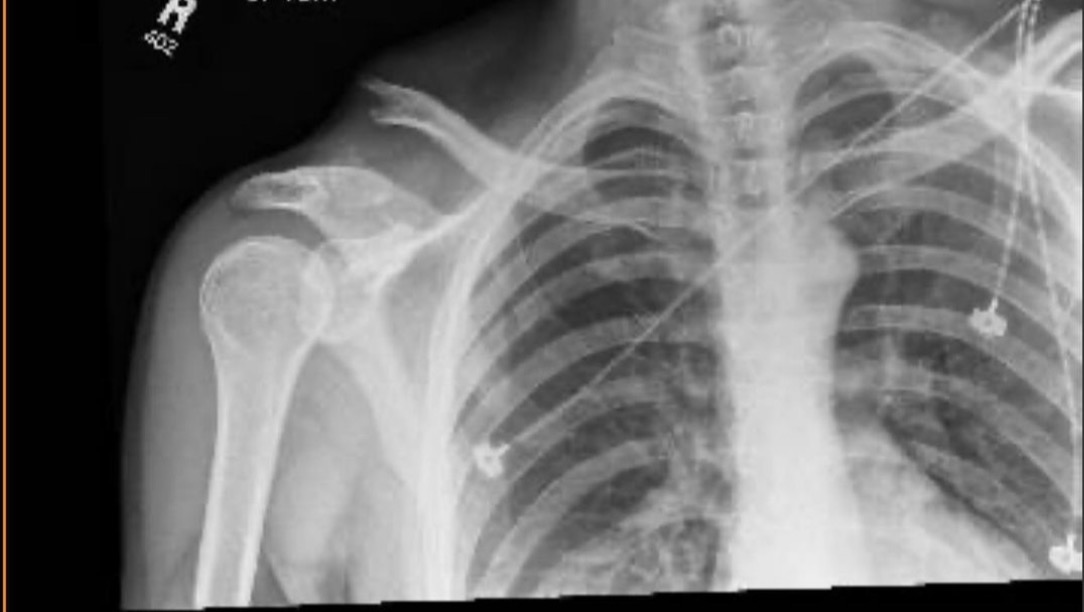

Hey y’all just a lil update: So I was in a bike accident 8 days ago making the 3.5 mile journey home at around 1:30am. A car came in a little too close in the lane I was in and I over corrected, hopped the curb, lost traction and flew into a rock(s?). 8 broken ribs and snapped my clavicle as well as the tendons that held it together. My phone was lost in the accident and the car didn’t stop, I searched around for the phone in the dark for a bit gave up and started walking my bike towards home. Things get fuzzy as the pain starts making its way through the adrenaline but I eventually met a seriously nice parking attendant that gave me a ride the last couple miles home. Made it to the hospital by around 2:30am and much of that last hour I cannot remember. After 36 hours in the hospital I was able to go home and wait for surgery, I can’t explain the pain but having a bone sticking out of your neck and feeling your shoulder separate every time you move is unreal, it’s also not lost on me that I’m lucky to be alive at all to even experience that. 4 days later (yesterday) and surgery went well by all accounts, I now have a dead persons tendons holding my bones together so at least it kinda fits the season. Be safe y’all I love you- I’ll be out of work for a while and have costs associated with the accident building up, hate to do this and never thought it would be me asking for help.

Broken collarbone pictured below: